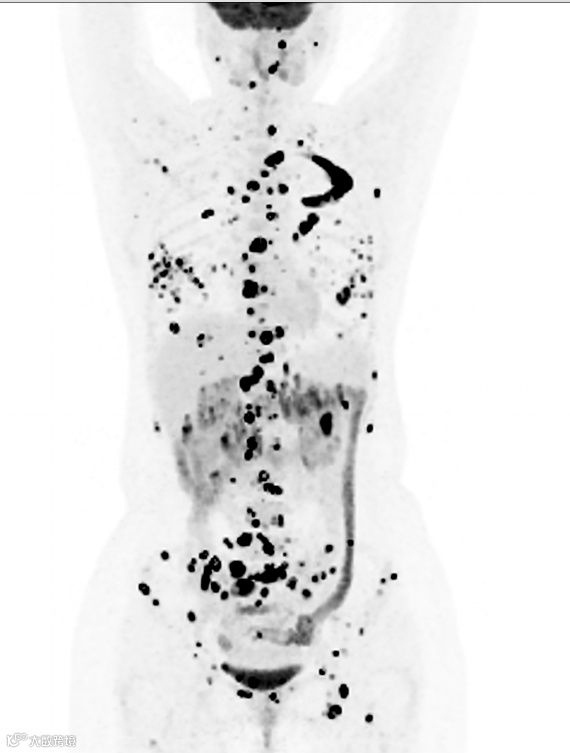

全身骨显像

核素骨显像最重要的优点是对骨病的诊断具有较高的灵敏度。以转移性骨肿瘤为例,一般比X线骨片和CT早3-6个月,有的甚至早1年。因此,核素骨显像已成为早期诊断骨转移的重要手段。对恶性肿瘤患者治疗前分期及治疗后随访具有重要意义。

优点:1.对原发性和继发性骨骼系统疾病诊断的灵敏性高;

2.一次注射显像剂,可进行全身、动态和多时相、局部(包括多体位)、断层显像,能较全面地观察疾病,尤其是多发病变,为疾病的诊断和鉴别、明确进一步检查、制定有效和正确的治疗方案提供依据;

3.通过反映骨代谢、血流等变化,评价病情变化和治疗疗效,预测预后;